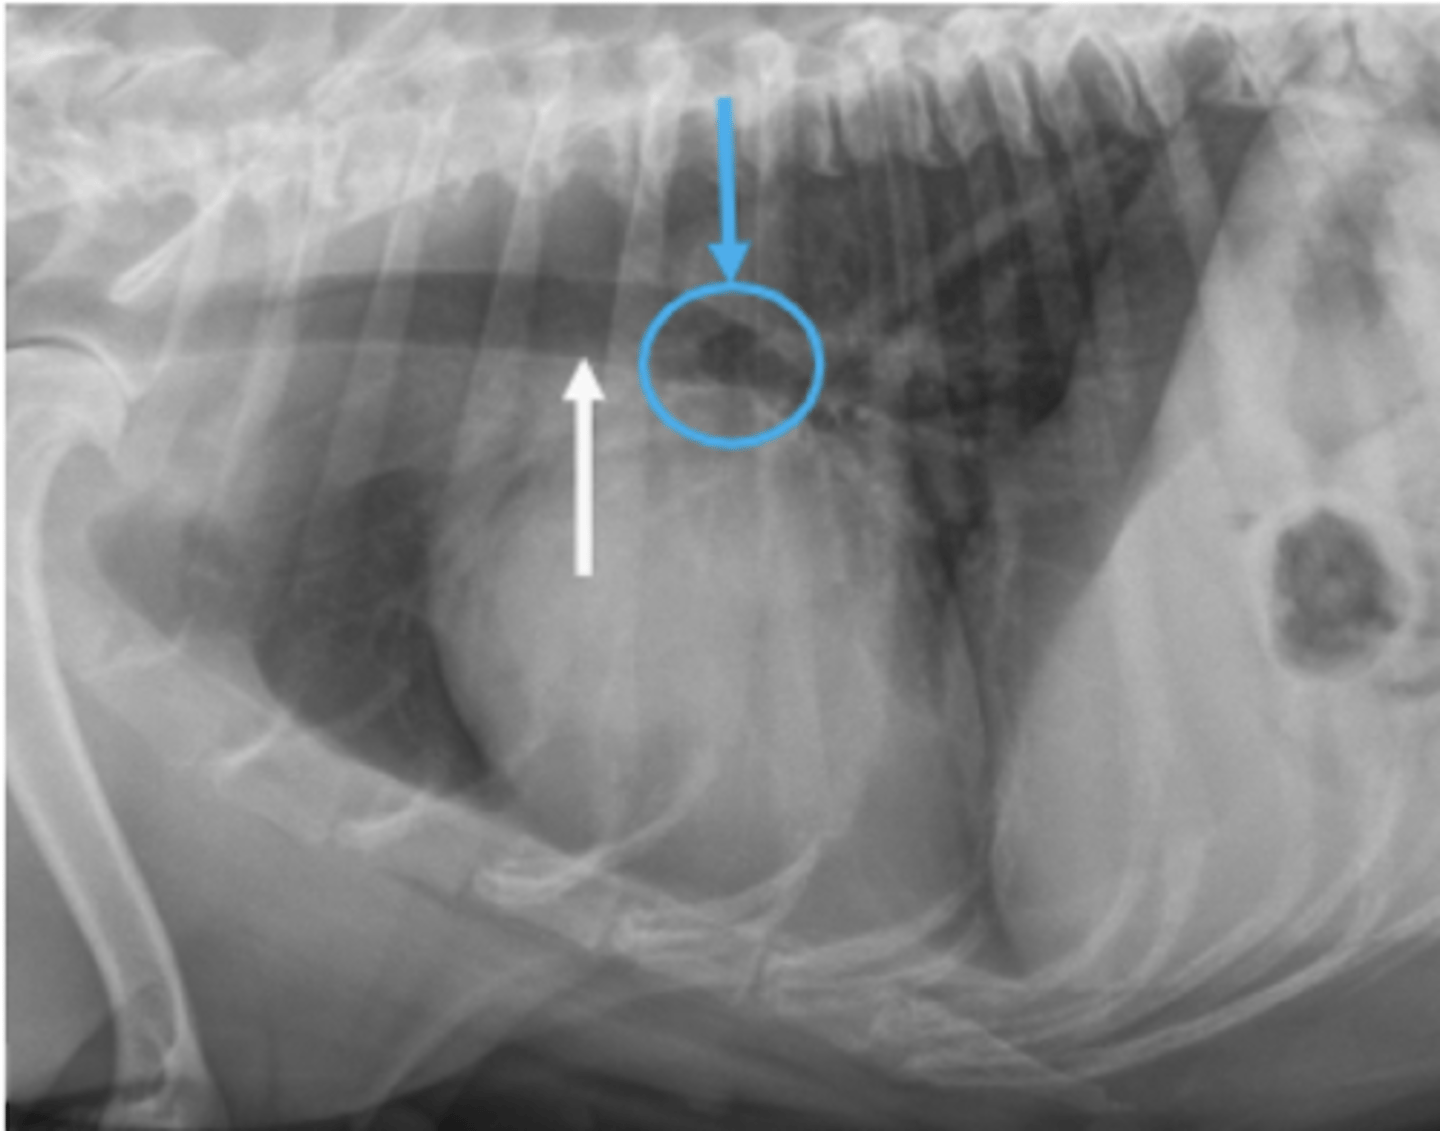

dilatación-torsión gástrica

patología: